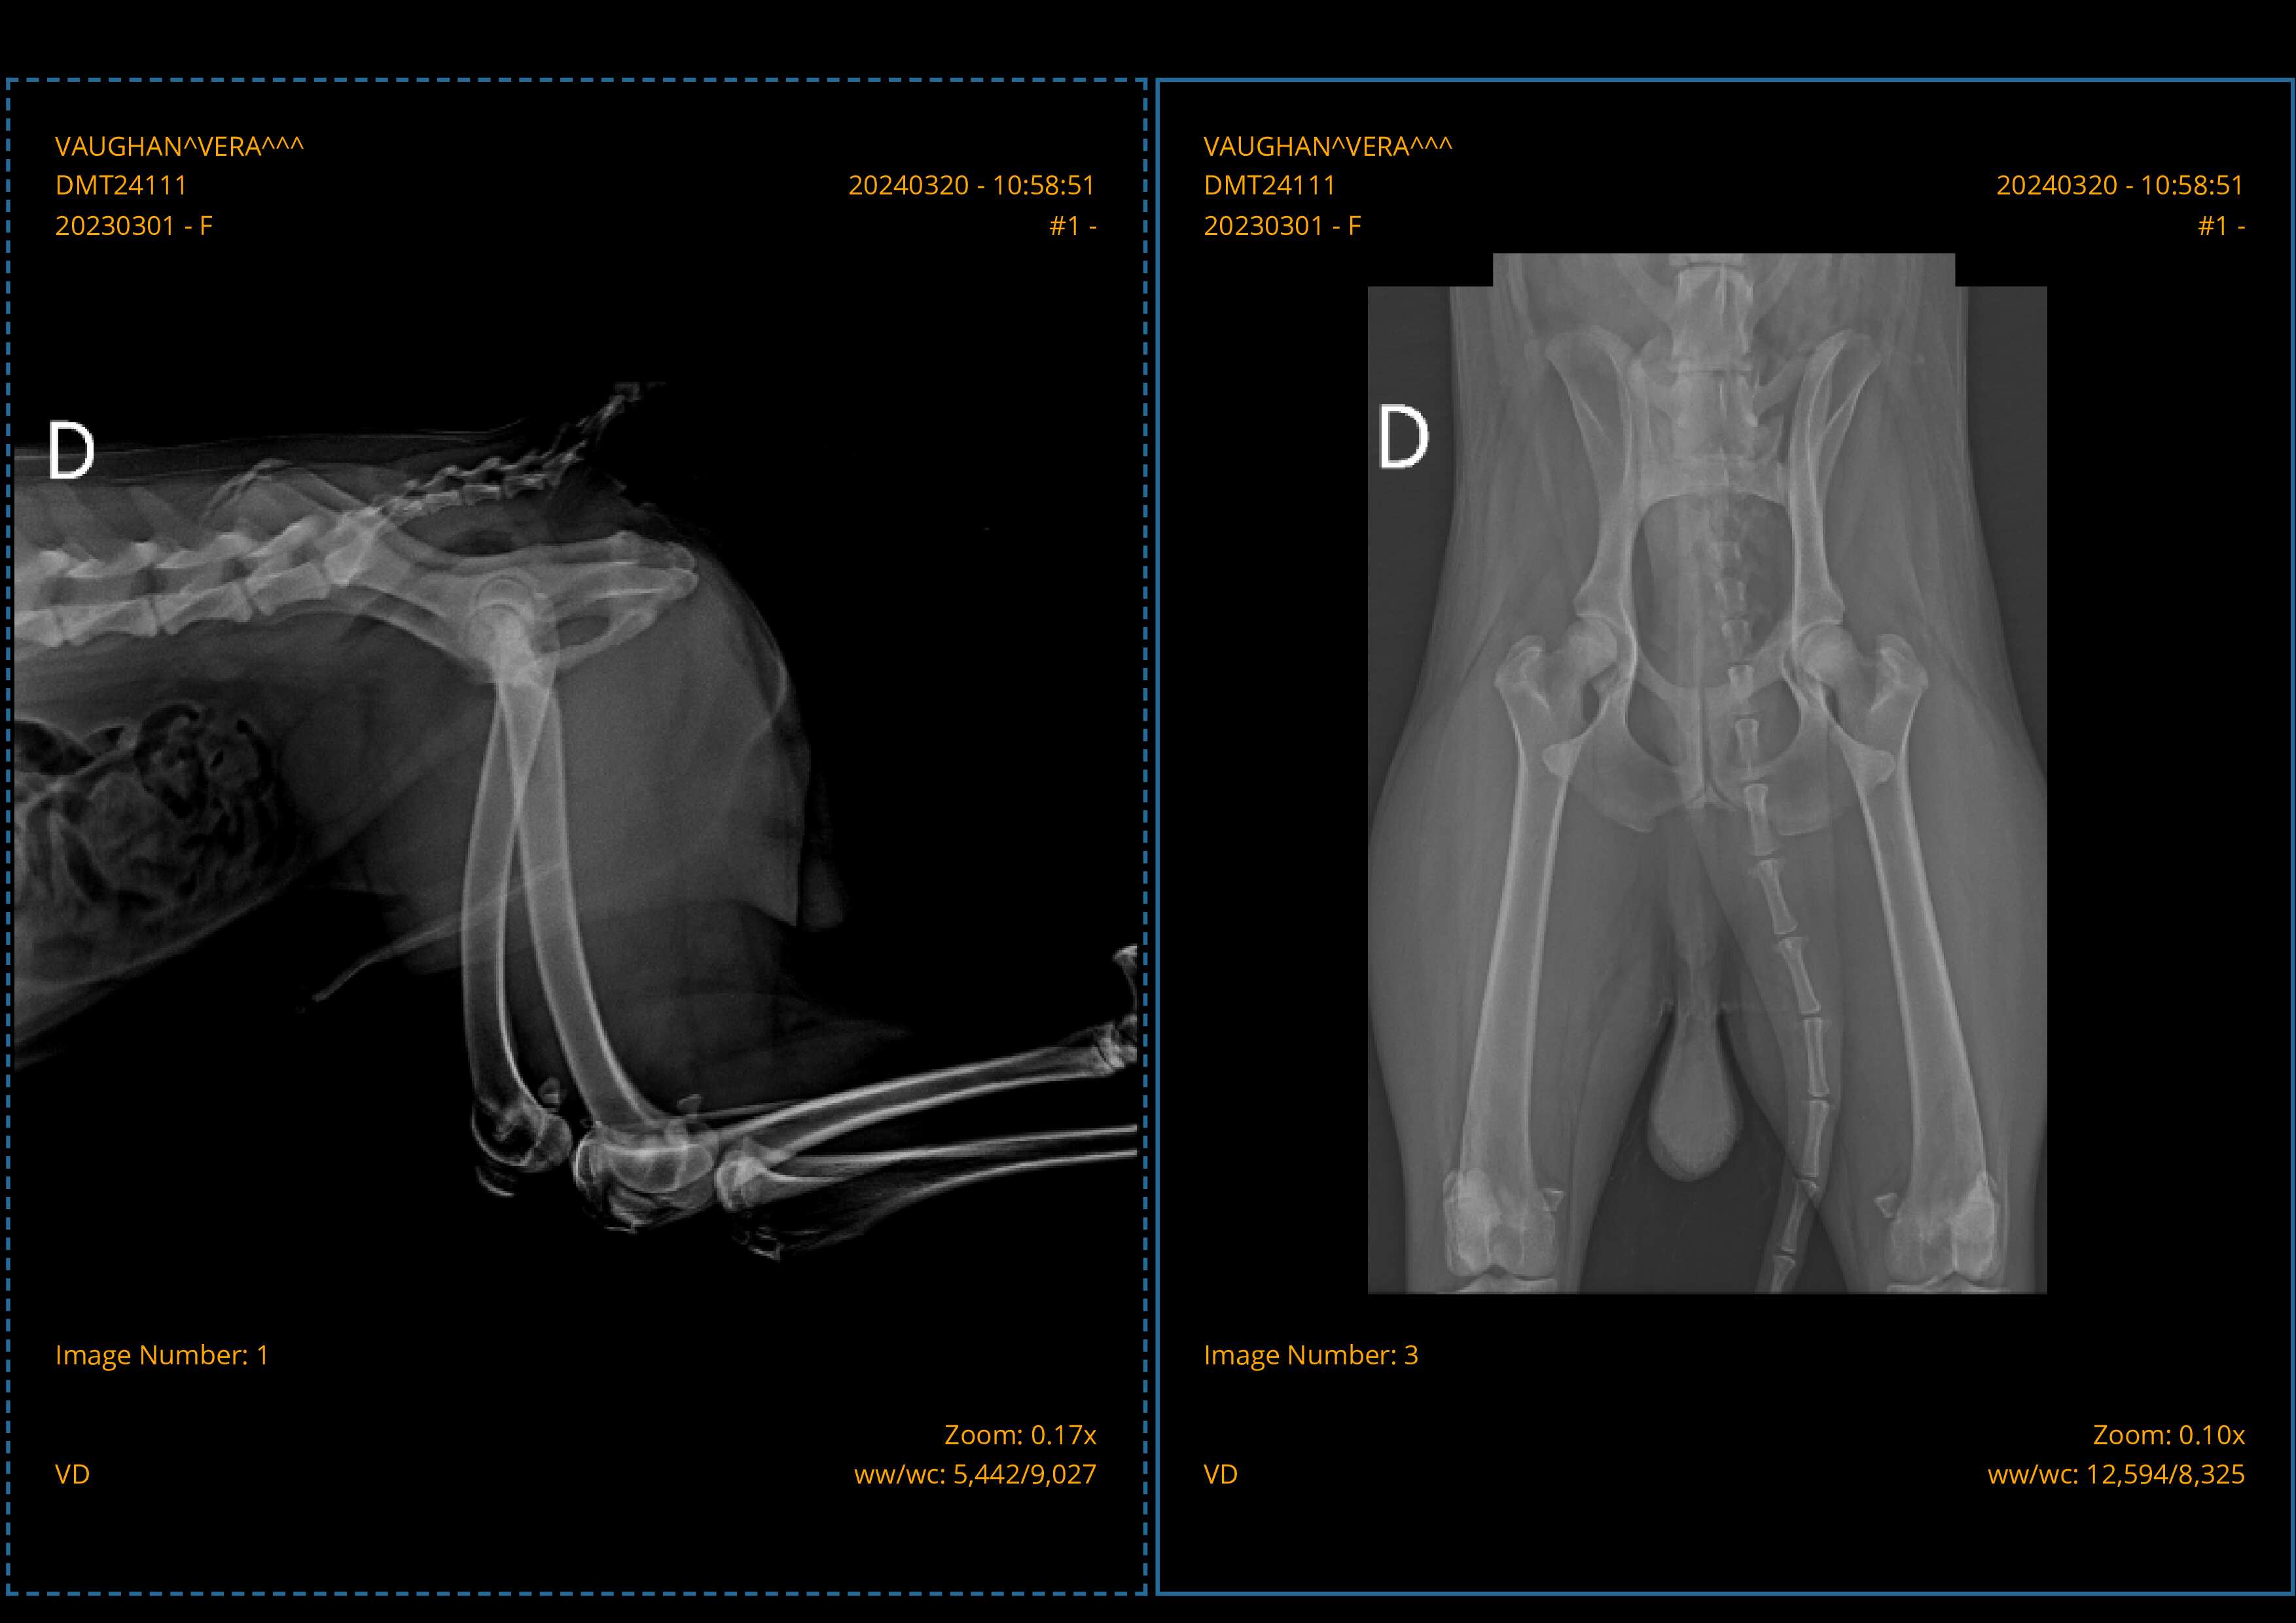

- HD 12 MESES – HD -+/- A